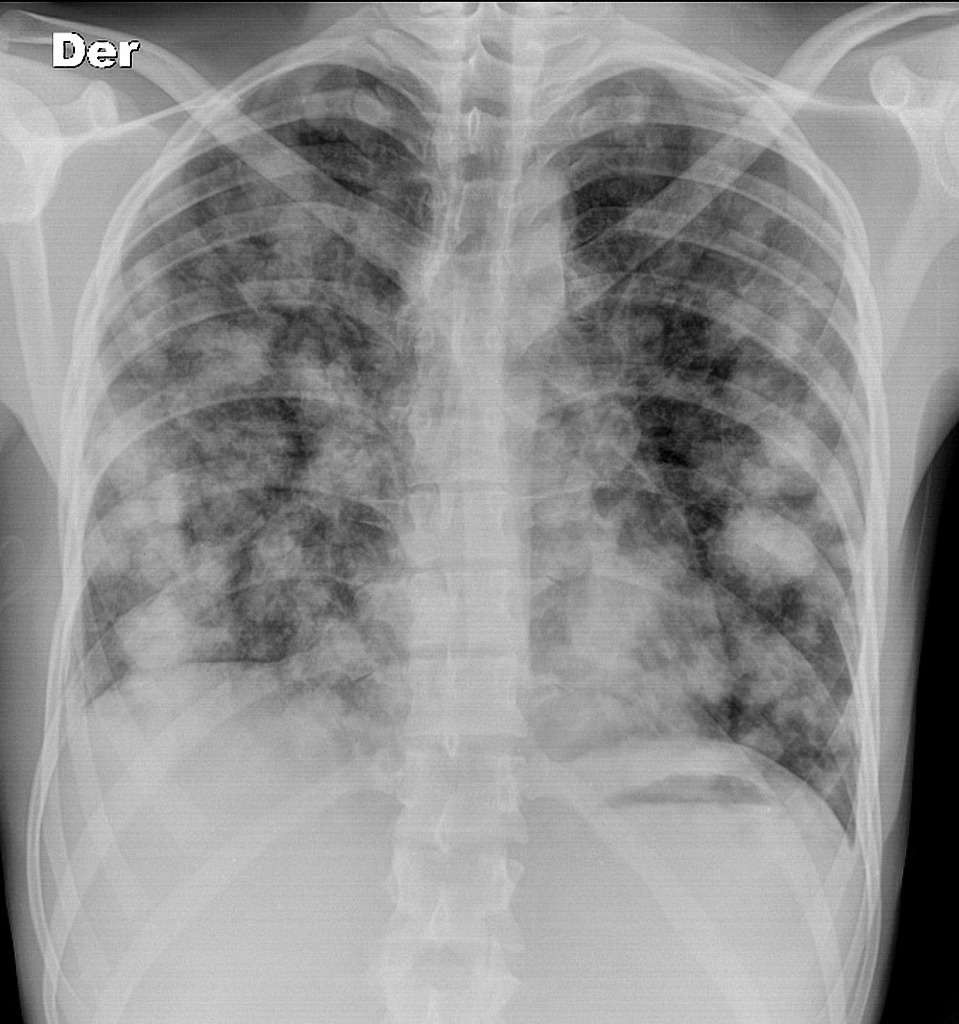

Miliary TB

Miliary TB Haematogenous dissemination

• Diffuse tiny nodules throughout both lungs (miliary pattern).

• May have associated involvement of liver, spleen, brain, etc.